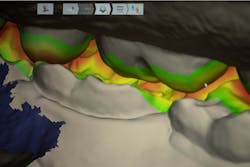

After a thorough evaluation of his clinical presentation, radiographs, and intraoral scan, it was evident that the discomfort was due to exposed dentin. The intraoral scan confirmed there was adequate interocclusal space to restore the eroded tooth structure with a minimally invasive approach (figure 2). All options were reviewed with the patient, and it was mutually agreed upon to address his chief complaint in this manner. Proper isolation is critical for reliable bonding.

Caries lesions were removed and air abrasion was employed to remove impurities on the unprepared tooth surfaces and create increased surface area for bonding. Preparation of the class II carious lesions revealed demineralization on the adjacent tooth structure (figure 3). When lesions such as these are discovered, dentists are often at a crossroads whether to intervene or monitor the area for progression. It is my experience that these early caries lesions can be predictably arrested with resin infiltration (figure 4), and that no intervention usually results in the progression of caries.

In this case, lateral access was achieved by the preparation of the adjacent teeth as part of the proposed treatment plan. Early caries lesions that are noted on radiographs that are not accessible in cases such as this one can be accessed by placing an orthodontic spacer. This patient was restored with direct composite bonding (figure 5) and these restorations have proven to have a favorable long-term outcome (figure 6).